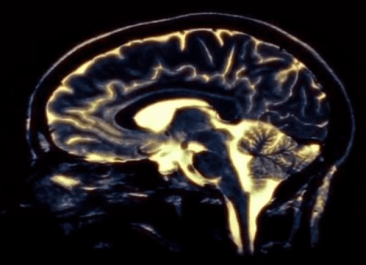

Die rasanten wissenschaftlich-technischen Entwicklungen des 19. Jahrhunderts und deren ökonomischen Folgen zündeten nicht nur das Feuer der 1848er Revolution, an der Meyer teilnimmt, sondern entfesselten auch den Streit zwischen Somatikern und Psychikern in der Medizin, der bis heute albern aufflammt. Sein Futter bezieht er aus Kausalitätsfragen. Zieglgänsberger (Max-Planck-Institut München) erklärte die Rolle von Psyche und Körper bei der Entstehung von Schmerz (z.B.) einmal so: Ihre rechte Hand ist der Körper, die linke die Psyche. Klatschen Sie in die Hände. Und nun sagen Sie, welche Hand den Schall gemacht hat. Heißt: Systemisch, nicht kausal denken. Inzwischen kann man mit der Positronen-Emissions-Tomographie (PET) in den Kopf gucken. Davon hat gehirnLudwig Meyer – Irrenarzt, Forscher, Humanist – geträumt. Den Leuten in den Kopf gucken, damit man erkenne, was darin verkehrt ist, oder vielmehr, was sie leiden macht. Auch er denkt in Kausalzusammenhängen, wie wohl die meisten von uns. Die Frage nach dem Warum scheint uns inne zu wohnen wie der Wunsch nach göttlichem Schutz. (Dort endet sie ja auch.) Meyer quält sie nach dem Tod der geliebten Mutter und treibt ihn an. Er lernt, studiert mit preußischer Disziplin. Aber wie kann die Ordnung etwas so Unordentlichem wie dem Wahnsinn beikommen? Bei seinen Studien stößt er auf John Conollys No-restraint-Prinzip und ist begeistert. Freiheit für alle! Gleichgültig welcher Geist sie be- oder entseelt. 1864 gründet er die erste moderne Heil- und Irrenanstalt in Hamburg. Eine Bibliothek, eine Werkstatt, ein Konzertsaal werden eingerichtet. Die Irren dürfen im Garten wandeln und arbeiten, und so irre sein, wie sie wollen. Meyer begegnet ihnen mit Freundlichkeit und Respekt. Er redet mit ihnen, lange, geduldig, angemessen. Dass diese Haltung zu Konflikten mit Staatsbeamten und Neidern führt, liegt auf der Hand. Meyer kämpft weiter. Gegen Dummheit, Bosheit und Ignoranz. Julia, seine Schwester, steht ihm mit ihrer stabilen Heiterkeit zur Seite, denn auch die Liebesbeziehung zu der treppe1Schauspielerin Fanny Nielsen ist fragil. Dem strengen Vater verzeiht er nicht, dass er seine Mutter ins Irrenhaus brachte. Einfühlsam erzählt Kollender von der Ahnungslosigkeit, von Gehorsam, von Hilflosigkeit der kranken Frau gegenüber, die des Vaters Entscheidung begründeten. Dem Autor gelingt es, die Atmosphäre jener Zeit, den Aufbruch, die Konflikte, die Zwänge sichtbar zu machen, er lässt sie außerordentlich modern erscheinen. Facettenreich und lebendig sind seine Charaktere, reich bebildert seine Schilderungen der Umstände. An verschiedenen Stellen des Romans scheint die Frage auf: Was ist normal? Gerade an den Kanten gesellschaftlicher Umbrüche stellt sie sich, im Schatten des deutsch-dänischen Krieges zum Beispiel, der wie alle Kriege jede Menge Kriegszitterer und Versehrte produzierte. Sehr aktuell bleibt die Fragestellung nach dem Grund des Wahnsinns. Bis heute ist keiner dahinter gekommen. Oliver Schubbe (Traumainstitut Berlin) sagte einmal in etwa: Schau dir den Sternenhimmel in der Wüste an. So viele Sterne du siehst, so viele Hirnzellen gibt es. Die sind alle miteinander vernetzt. Keiner kann die Hirnfunktionen erfassen, nicht mit Neurobiologie und nicht mit PET. Es ist völlig unmöglich, die Unendlichkeit aufzuklären.